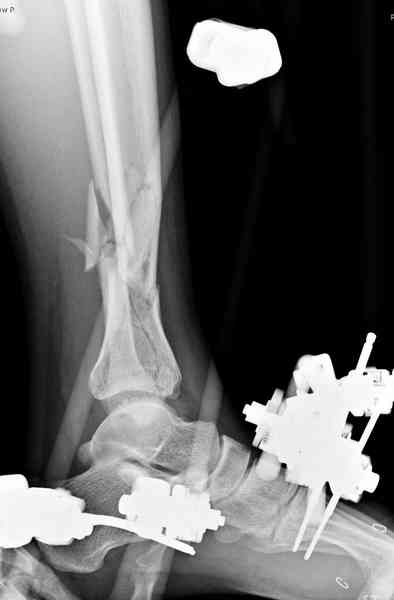

Такое большое количество неудовлетворительных результатов внутренней фиксации взрывных переломов голеностопного сустава, вызвало пересмотр классических методов лечения и появлению работ, в которых ограниченная внутренняя фиксация перелома большеберцовой кости сочетается с наружной

фиксацией. Такая комбинация улучшила процент удовлетворительных результатов до 67-81%, уменьшила количество нагноения глубоких слоёв раны до 8%, однако спицевые нагноения сохраняют по данным некоторых авторов довольно высокий процент – 37%, а потеря редукции составляет 11% (Dickson, Montgomery, and Field, Court, Brown et).

2-ой группе (55%) был произведен одномоментный минимально инвазивный остеосинтез с длительной фиксацией голеностопного сустава аппаратом внешней фиксации.

3-ей группе (16%) на первом этапе наложен аппарат, для восстановления мягких тканей, на втором этапе произведён минимально инвазивный остеосинтез, с последующей разработкой и частичной нагрузкой в аппарате.

На сегодняшний день, стандартом лечения переломов pilon являются протоколы, включающие наложение наружных фиксаторов на 1-3 недели для поддержания длины и восстановления мягких тканей с последующей закрытой или открытой репозицией перелома большеберцовой кости и фиксацией наружным аппаратом в комбинации с минимальной внутренней фиксацией или без неё, ± фиксация малоберцовой кости с помощью платы и шурупов. Голеностопный сустав фиксируется в аппарате 6-12 недель, после чего начинается его разработка, общий срок фиксации в аппарате 12-16 недель, а для переломов проникающих до диафиза – 6 месяцев.